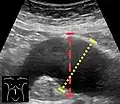

An abdominal aortic aneurysm is usually diagnosed by physical exam, abdominal ultrasound, or CT scan. Plain abdominal radiographs may show the outline of an aneurysm when its walls are calcified. However, the outline will be visible by X-ray in less than half of all aneurysms. Ultrasonography is used to screen for aneurysms and to determine their size if present. Additionally, free peritoneal fluid can be detected. It is non-invasive and sensitive, but the presence of bowel gas or obesity may limit its usefulness.[30] CT scan has nearly 100% sensitivity for an aneurysm and is also useful in preoperative planning, detailing the anatomy and possibility for endovascular repair. In the case of suspected rupture, it can also reliably detect retroperitoneal fluid. Alternative less often used methods for visualization of an aneurysm include MRI and angiography.[31]

39. ^ Timothy Jang (2017-08-28). "Bedside Ultrasonography Evaluation of Abdominal Aortic Aneurysm - Technique". Medscape. Archived from the original on 2018-01-25.

40. ^ "UOTW #35 - Ultrasound of the Week". Ultrasound of the Week. 27 January 2015. Archived from the original on 9 May 2017. Retrieved 27 May 2017.